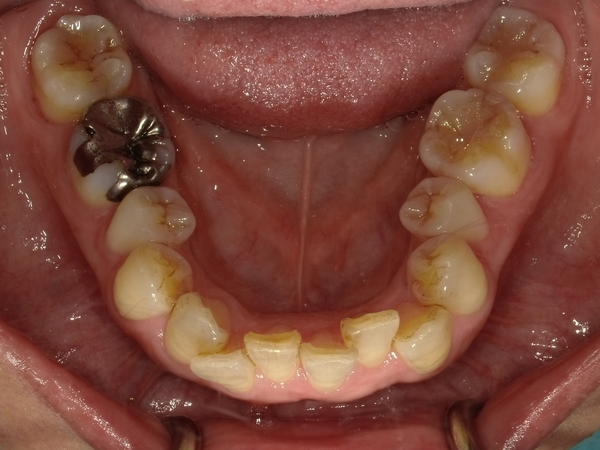

◯ご相談内容:歯がでたり引っ込んでいたりする◯矯正の種類:マウスピース型矯正「インビザラインGO」◯治療期間:17週間◯治療費用:44万円(税込)